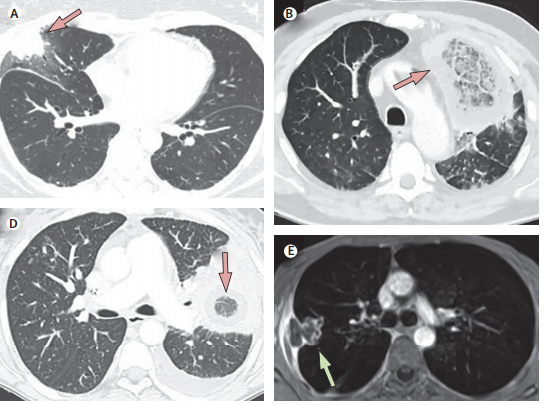

以下為“指南”公示的一些常見臨牀表徵圖示:

**A.**車禍後左腿廣泛皮膚型毛黴菌病;

**B.**沒有進行治療和病情控制的糖尿病患者,起病6天,出現皮膚紅斑,上瞼下垂,瞼水腫,眼部活動受限和右上頜疼痛;

**C.**沒控制病情的糖尿病患者,起病7天,出現眼瞼腫、發紅和海綿竇綜合徵;

D. 同樣是沒有控制病情的糖尿病患者,起病8天,出現壞死性化膿性上顎潰瘍和海綿竇綜合徵;

E. 2歲女嬰,急性淋巴性白血病,發生鼻眶腦型毛黴菌病,最終死亡;

F. 52歲化療後男性,持續中性粒細胞下降,發生鼻竇炎和皮膚壞疽;

G. 毛黴菌病中的典型皮膚病變——黑痂,患者為造血幹細胞移植受者。

此外,影像學檢查也可發現臟器內的明顯感染灶——

箭頭所指的部位皆為CT下看到的感染灶,“指南”提示MRI和B超同樣可以用來檢查毛黴菌病的感染情況。